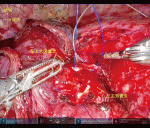

ロボット支援下手術における利点は先に述べた術野固定,三次元拡大視野,巧緻性が挙げられる.一方で触覚の欠如による力感のコントロールが課題である.ゆえに気管支形成術において縫合は容易いが,結紮が難儀である.われわれは結紮の回数を減らすため胸腔外で予め作成した両端針を用い連続縫合を行っている.ロボット支援下気管支形成術では開胸や胸腔鏡に比較し,短い手術時間,少ない出血量,在院日数の短縮,同等の腫瘍学的予後が得られたと報告されており,ロボット支援下気管支形成術は今後増加すると考えられる1).当科ではロボット支援下胸壁合併切除術2)やロボット支援下肺動脈形成術3)など拡大手術を実践している.ポート配置や手術手順を工夫することで,精密な操作だけでなく,術後疼痛や整容性の観点から有用になり得る.低侵襲性を追求していく上で手術支援ロボットを使用したアプローチ方法や手術方法を確立していくことが求められており,施設間で手技の工夫を共有していくことが肝要である.

ロボット支援下気管支形成術は,ロボット手術の特性を活かし固定された三次元拡大視野,巧緻性により精密な手術が可能である.一方で触覚の欠如による力感のコントロールが課題であり,さらなる症例の蓄積が望まれる.